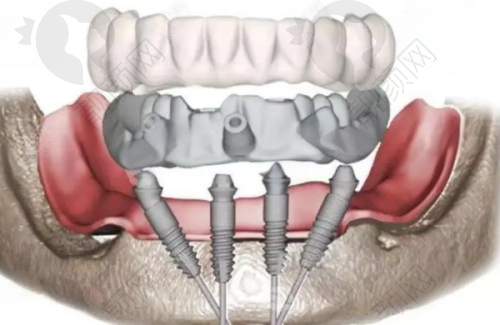

All - on - 4 全口种植牙 80000 元起(倾斜植入技术,4 颗植体修复全口),通过倾斜植入植体,减少了植体数量,降低了成本,同时缩短了治疗时间。

All - on - 6 全口种植牙 100000 元起(6 颗植体提供更强支撑力),6 颗植体能为全口牙齿提供更稳固的支撑,适合对牙齿稳定性要求较高的患者。